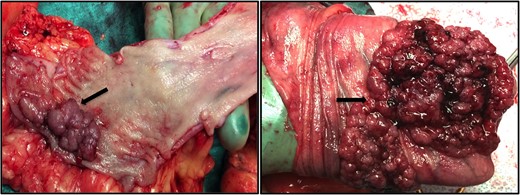

A 63-year-old morbidly obese female (BMI of 62.2 kg/m2) who underwent a JIB in 1973, presented to our surgical clinic in December of 2013 with persistent morbid obesity as well as vague gastrointestinal complaints, particularly the sensation of bloating. Her medical history includes hypertension, diabetes mellitus type 2, hyperlipidemia, chronic kidney disease, arthritis, congestive heart failure, gout, fatty liver disease, history of a deep vein thrombosis and pulmonary emboli. The patient denies any known family history of colorectal cancer or familial polyposis syndromes. During a previous screening esophagogastroduodenoscopy and colonoscopy in 2010 the patient was found to have reflux induced esophagitis with a normal stomach and duodenum. On colonoscopy, she was found to have multiple adenomatous polyps throughout the colon, without any evidence for malignancy. The patient unfortunately was lost to follow-up until she was seen in our minimally invasive general and bariatric surgery clinic in December of 2013. After our assessment, the patient was referred back to gastroenterology for further evaluation based on prior findings of multiple colonic polyps from 2010. A repeat colonoscopy in February of 2014 identified multiple tubular adenomatous and tubulovillous polyps measuring 3–30 mm in size throughout the colon (Fig. 2). Due to the extent of the colonic polyposis and persistent morbid obesity, the patient was taken to surgery for a total abdominal colectomy and low anterior resection with an end ileostomy by the colorectal surgical team, reversal of her previous JIB, and vertical sleeve gastrectomy. A total of thirteen colonic polyps were found in the resected specimen ranging in size from 1.4 to 7.6 cm. Pictures of the gross pathology for two of the larger polyps are shown in Fig. 3. Histopathologic analysis from a 1.4 cm polyp in the ascending colon revealed an invasive adenocarcinoma (Fig. 4). Twelve benign lymph nodes were also found in the resected specimen. The patient tolerated her immediate post-operative course well, however, she expired on post-operative day 67 due to septic complications including pneumonia.